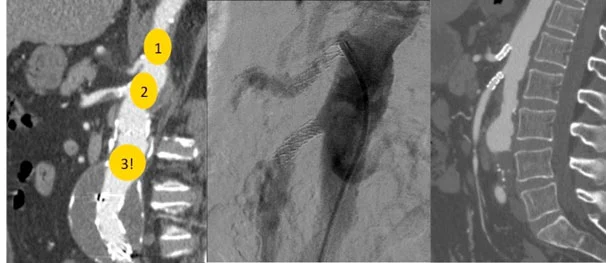

Tre vasi principali si occupano di vascolarizzare gli organi addominali e l’intestino:

- Tronco celiaco: irrora l’esofago, lo stomaco, il duodeno prossimale, il fegato, la colecisti, il pancreas e la milza.

- Arteria mesenterica superiore: irrora il duodeno distale, il digiuno, l’ileo e il colon fino alla flessura splenica.

- Arteria mesenterica inferiore: irrora il colon discendente, il sigma e il retto.